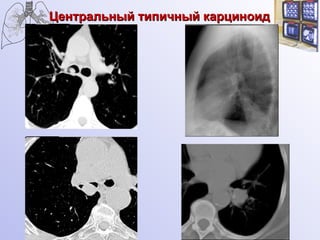

Карциноид центральный

Центральный типичный карциноид